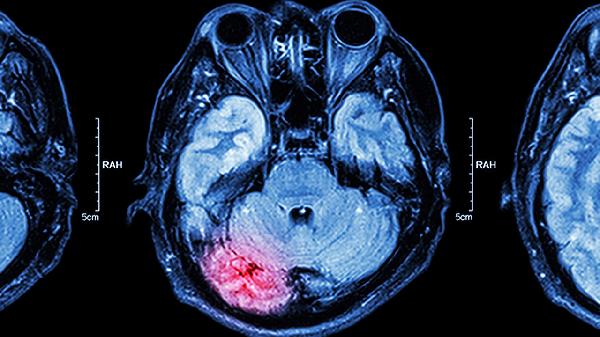

单纯疱疹病毒1型是成人病毒性脑炎最常见病原体,病毒潜伏于三叉神经节,当免疫力下降时沿神经轴突侵入脑实质。典型表现为颞叶及额叶局灶性损害,脑脊液PCR检测可确诊。临床需早期使用阿昔洛韦静脉治疗。

乙型脑炎病毒经蚊虫叮咬传播,主要累及丘脑、基底节等深部灰质。急性期出现高热、意识障碍及肌张力增高,恢复期可能遗留帕金森样症状。疫苗接种是最有效预防措施。